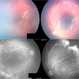

- retinopathy of prematurity, aggressive posterior retinopathy of prematurity (APROP)

- Premature baby referred for ROP evaluation. HALF ZONE 1 was only vascularised, Patient was given Inj Anti-Vegf follwed by ROP Laser after 1 week